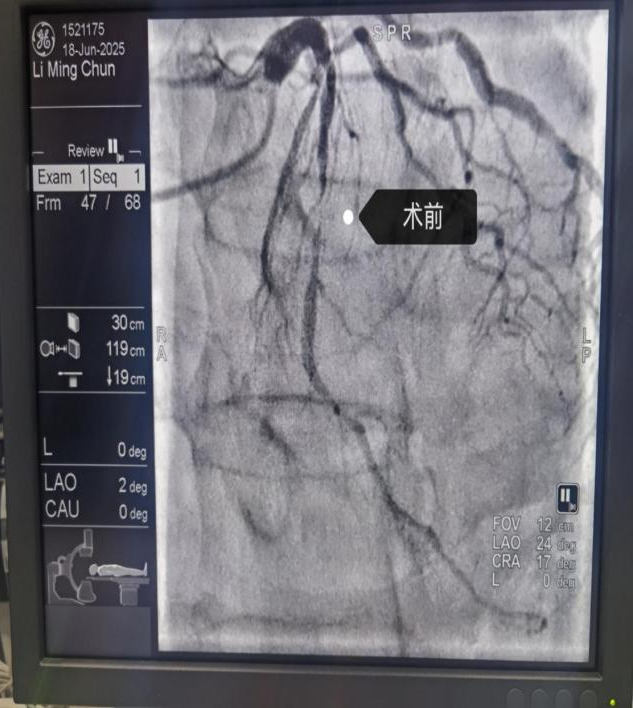

近期科室开展手术患者影像

冠状动脉造影术是一种微创介入诊断技术,通过向心脏冠状动脉注入造影剂,并在X射线透视下显影,精准评估冠状动脉是否存在狭窄、堵塞或畸形。它是诊断冠心病的“金标准”。通常从手腕桡动脉或大腿股动脉插入导管,将细软造影导管沿血管送至冠状动脉开口,注入造影剂,通过DSA实时成像,显示血管形态与血流情况。

近期重庆三峡医专附属中医院心血管病科连续开展多例冠状动脉造影术+支架植入术,该类型手术的常规开展,标志着医院心血管病科从传统中西医结合内科治疗心血管疾病进入了中西医结合+介入手术治疗的新阶段。